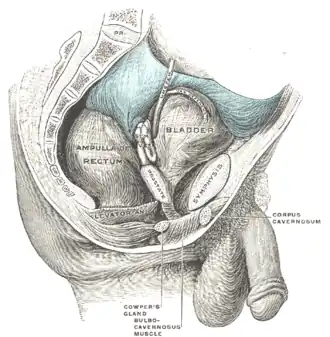

Male pelvic organs seen from right side.

Male pelvic organs seen from right side.